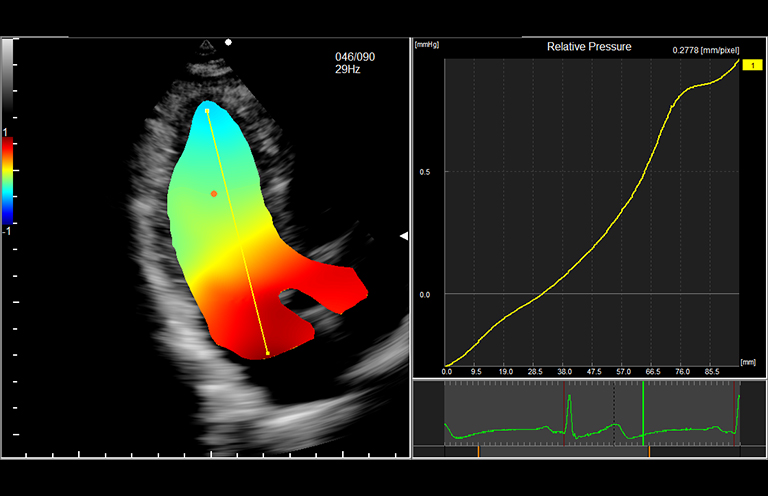

Aplicación: Cardiología

Función/análisis: VFM/Tensión de elasticidad de pared

Comentarios: Corazón

Función/análisis: VFM (presión relativa)